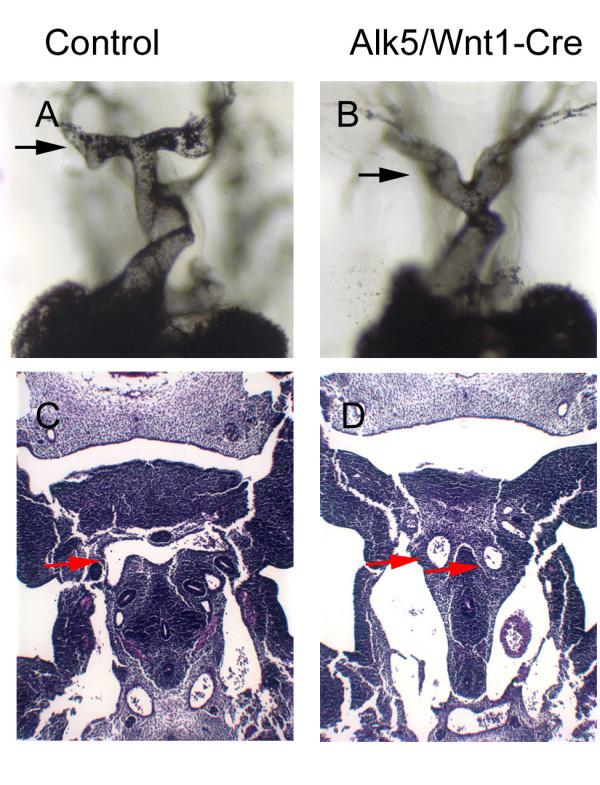

RESULTS

We deleted the TGF-beta type I receptor Alk5 specifically in the mouse neural crest cell lineage. Failure in signaling via ALK5 leads to severe cardiovascular and pharyngeal defects, including inappropriate remodeling of pharyngeal arch arteries, abnormal aortic sac development, failure in pharyngeal organ migration and persistent truncus arteriosus. While ALK5 is not required for neural crest cell migration, our results demonstrate that it plays an important role in the survival of post-migratory cardiac neural crest cells.

CONCLUSION

Our results demonstrate that ALK5-mediated signaling in neural crest cells plays an essential cell-autonomous role in the pharyngeal and cardiac outflow tract development.